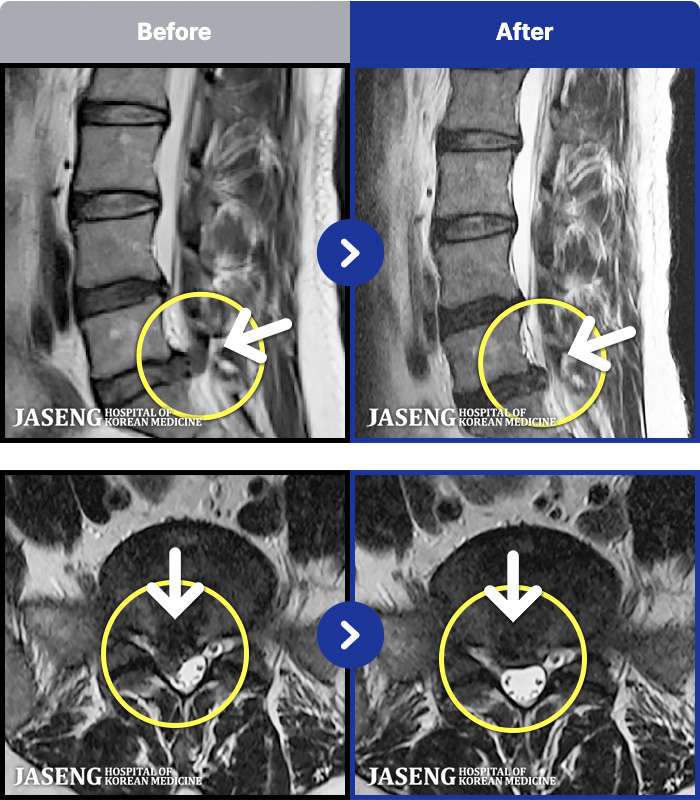

MRI ũ ʸ Ȯϼ.

ȯںп Ǹ ǿ ԿǾ, ο ġ ۿ Ƿ ġḦ Ͻñ ٶϴ.